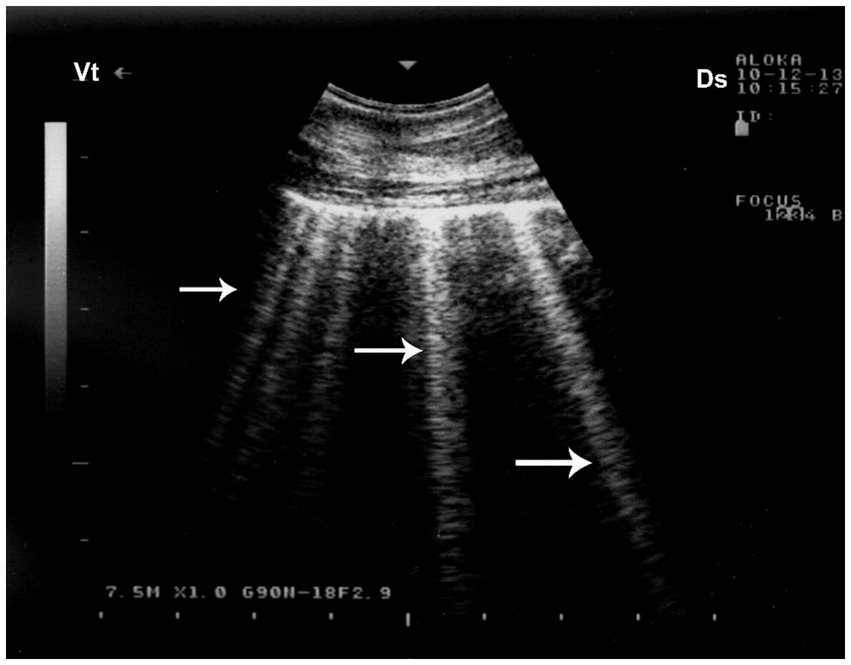

Ultrasonography plays a pivotal role in the prompt diagnosis of pneumothorax, particularly in field settings where conventional imaging is limited. The absence of normal lung sliding—a shimmering motion at the pleural line due to apposition of visceral and parietal pleura—is a hallmark sonographic sign of pneumothorax (8). In camels, thoracic ultrasonography is especially valuable due to their large thoracic volume and the difficulty of obtaining clear radiographic images in adult animals. Early detection through ultrasonography facilitates timely intervention, such as thoracocentesis or surgical management, significantly improving clinical outcomes. Ultrasonographic evaluation in camels with pulmonary emphysema reveals numerous comet-tail artifacts—bright, closely spaced echo bands originating at the lung surface and extending perpendicularly into the lung parenchyma (32) (Figure 11).